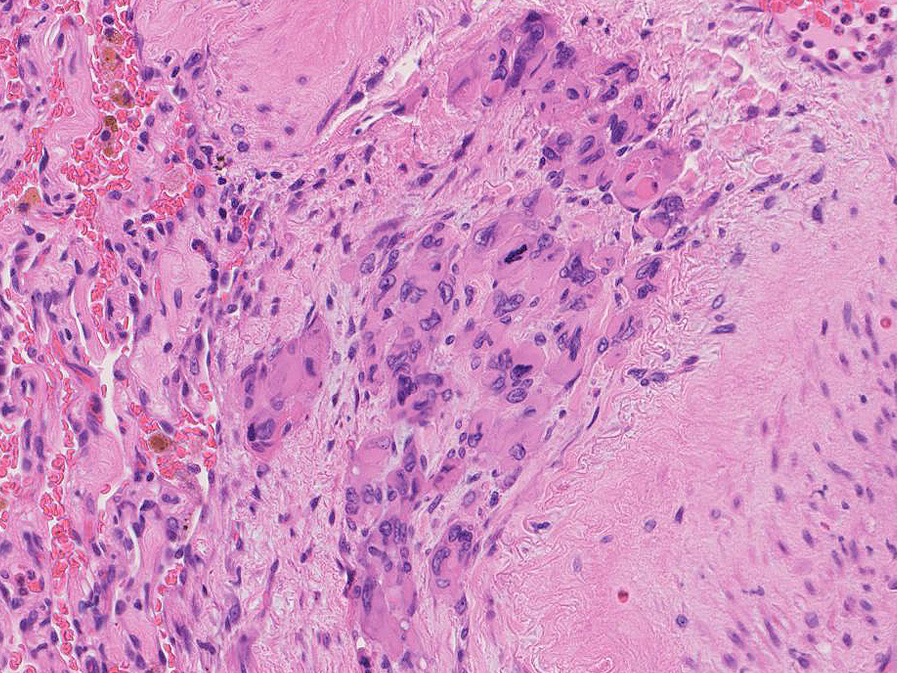

左図:腺腔様の裂隙が胞巣内にみられ, 凍結標本だと腺癌との区別がむずかしい。

右図:多型細胞や異型細胞が出現。核分裂像も異常に見える。